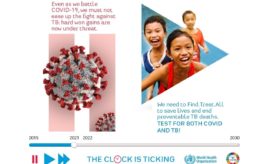

Οι άνθρωποι αυτοί δεν θα είχαν πεθάνει εάν η πανδημία δεν είχε διαταράξει την πρόσβαση στις υπηρεσίες Υγείας.

Μετά την πανδημία καταγράφεται σημαντική αύξηση στις μεταδοτικότερες μορφές φυματίωσης, προειδοποιεί.

Η μειωμένη πρόσβαση στο σύστημα Υγείας απειλεί την πρόοδο που έχει επιτευχθεί στον έλεγχο της φυματίωσης. Αυξάνονται τα κρούσματα...

Η 24η Μαρτίου έχει θεσπιστεί ως Παγκόσμια Ημέρα Φυματίωσης και παρά το γεγονός ότι με τα εμβόλια και τις...